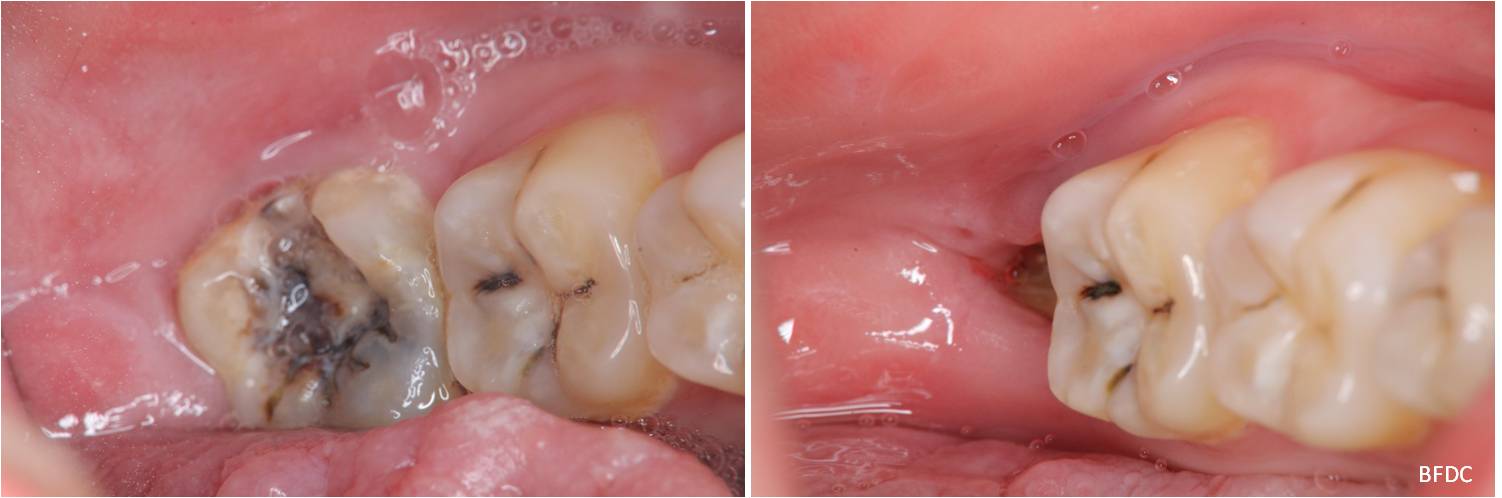

治療前,左下阻生齒深度蛀牙

術前、術後比較